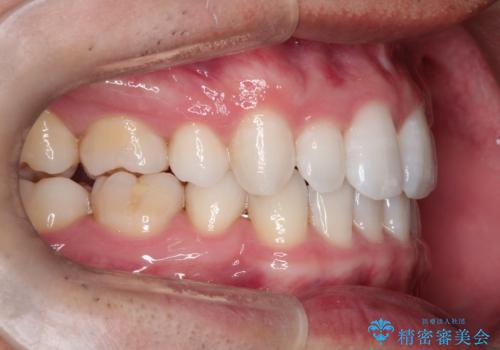

【インビザライン】笑った時の歯並びを綺麗にしたい

- 笑った時の歯の見え方を綺麗にしたいことを主訴に来院されました。

インビザラインにて治療を行なっております。